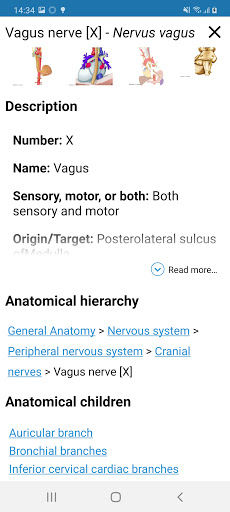

* Tablas introducidas en las definiciones de estructuras anatómicas para una mejor estructuración de datos

*Visibilidad mejorada de las definiciones de partes anatómicas

. *Navegación entre partes anatómicas usando enlaces de descripción.

la vista de detalles de una estructura anatómica ahora se muestran los términos relacionados